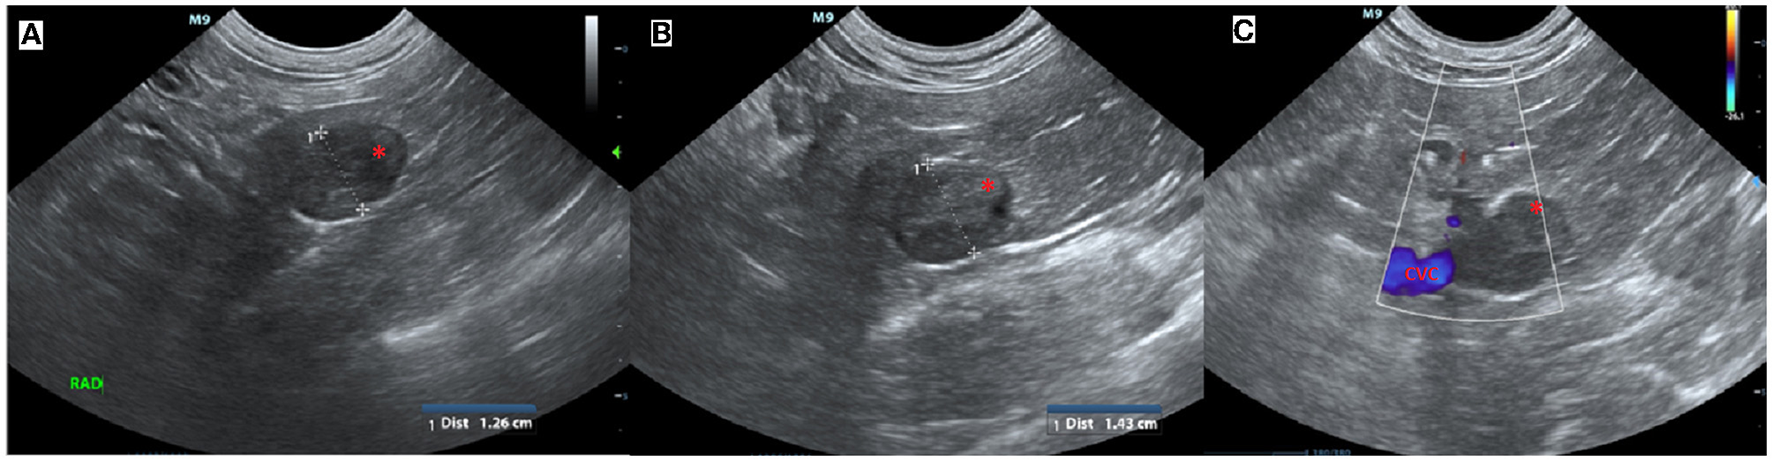

Upon exploratory laparotomy via ventral midline celiotomy under general anesthetic, the previous enterotomy site was visualized in the proximal to mid jejunum with omental adhesions. The right kidney and adrenal gland were palpable, however, they could not be visualized due to abundant retroperitoneal fat. Malleable retractors were utilized to improve visualization and the overlying fat was carefully dissected following incision into the peritoneum overlying the right kidney until the adrenal gland and associated mass were visible (Figure 3). The caudal pole of the right adrenal gland was enlarged, firm, spherical in shape, and had a smooth capsule with no signs of invasion into the surrounding structures. On manipulation of the mass, the serval's blood pressure increased to 170 mmHg systolic (mean arterial 130 mmHg). The right phrenicoabdominal vein was identified, ligated, and transected both cranial and caudal to the adrenal mass. Once fully excised en bloc using sharp and blunt dissection, the adrenal gland and associated mass were submitted in formalin for histopathological examination. Once the mass had been removed, the serval's hypertension was resolved and remained stable for the remainder of the general anesthetic. A coagulation panel was performed immediately following surgery, and the platelet count was decreased; however, there was platelet clumping noted on the blood smear (automated count likely to be spuriously decreased due to clumping, the manual count was subjectively normal). Recovery from anesthesia was uneventful. The sample was submitted for special immunohistochemical staining with Chromogranin A, as the intraoperative hypertension raised the possibility of an unusual pheochromocytoma.

Figure 3. Intra-operative image showing mass associated with the right adrenal gland (arrow). Cranial is at the top of the image and caudal is at the bottom of the image.